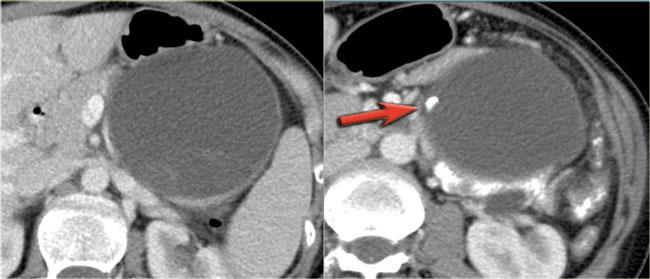

Hình CT bên trái là của một bệnh nhân có tiền sử viêm tụy.

Có hai nang đơn ngăn hay nang đơn giản.

Lưu ý thêm hình ảnh thâm nhiễm mỡ sau phúc mạc bên phải.

Chẩn đoán có khả năng nhất là nang giả.

Hình CT bên phải cho thấy một nang ở đuôi tụy ở một phụ nữ 36 tuổi, được phát hiện tình cờ qua siêu âm.

Nang có bờ dày không đều và chứa các thành phần đặc ‘không phụ thuộc trọng lực’.

Chẩn đoán có khả năng nhất là u nang tân sinh.